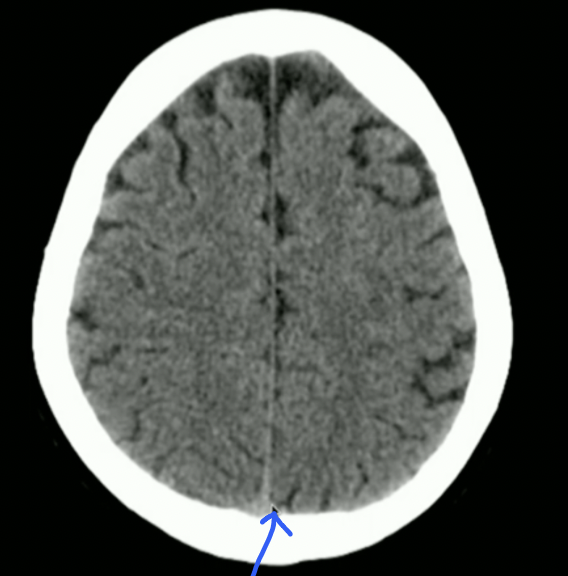

<p>Locate: Sulci, Grey Matter + White Matter</p>

Locate: Sulci, Grey Matter + White Matter

knowt flashcard image